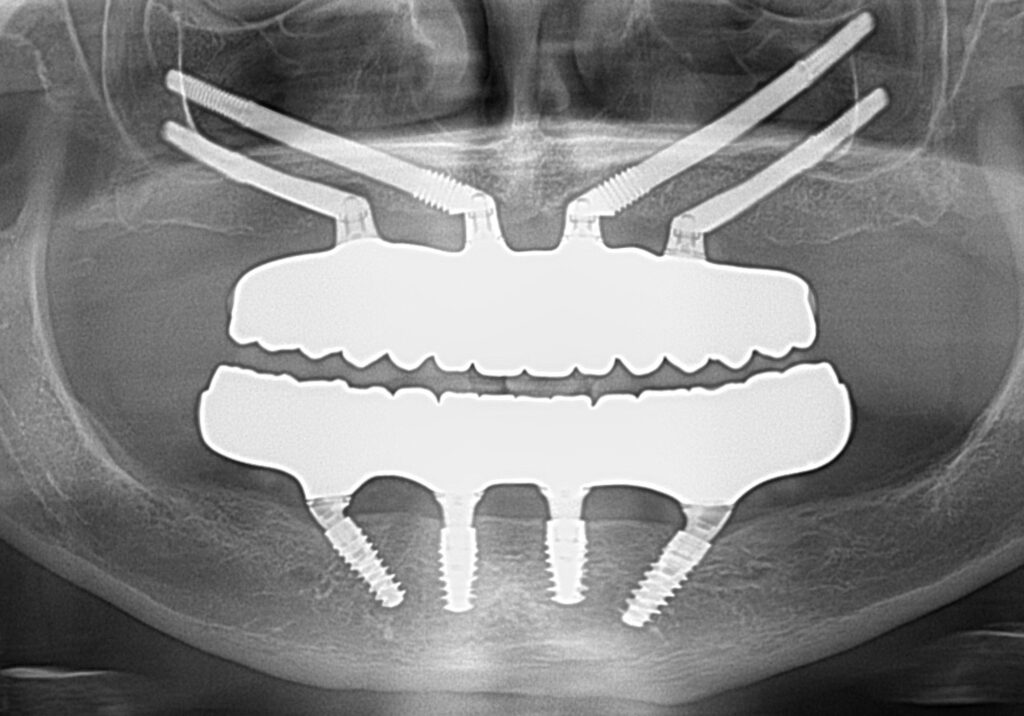

A selection of full arch fixed implant bridge patients after 5 years of wear